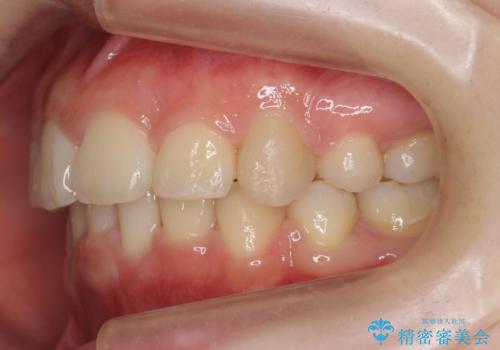

20代女性 出っ歯 口元を引っ込めたい

- 治療計画

- 出っ歯と前歯を気にして来院。

口元を下げたいとのことで、歯を抜いてワイヤー矯正を行いました。

口元、横顔の変化については、美容整形よりもゆっくりとした自然な変化が期待できます。

上下左右の小臼歯を抜歯しています。